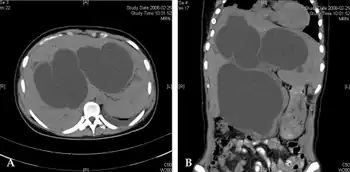

Diagnosis

.png)

Direct hyperbilirubinemia